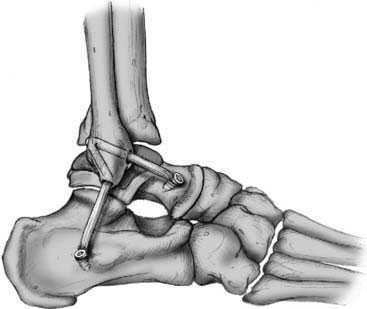

После восстановления латерального связочного комплекса по Брострому в модификации Голда и фиксации межберцового синдесмоза винтом производится оценка стабильности голеностопного сустава при помощи вальгус—стресс теста под контролем ЭОП.

Гипермобильность голеностопного сустава устранена, положение таранной кости остаётся неизменным несмотря на приложение вальгусной нагрузки.

В настоящее время существует 2 основных методики проведения трансплантата через малоберцовую кость. Либо делается 2 канала диаметром соответствующие трансплантату и образующие острый угол, либо делается один канал большего диаметра в который вставляется сложенный вдвое трансплантат. При этом фиксация в малоберцовой кости в первом случае осуществляется при помощи биотенодезных винтов, во втором случае фиксация происходит за счёт титановой пуговицы. Фиксация на таранной и пяточной кости в обоих случаях идентичная при помощи биотенодезных винтов.

После подтверждения нестабильности и устранения разрастаний синовиальной и рубцовой ткани переходим к этапу забора аутотрансплантата и его подготовки к последующей трансплантации. У транспланатата 2 плеча, сложенная вдвое часть погружается в канал малоберцовой кости, а «рукава» фиксируются в каналах таранной и пяточной кости соответсвенно в месте прикрепления передней таранно-малоберцовой и пяточно-малоберцовой связок.

После подготовки транспланата выполняется продольный доступ в проекции апекса латеральной лодыжки, из которого выделяется передняя таранно-малоберцовая связка, чаще всего она бывает частично замещена рубцом в зоне прикрепления к малоберцовой кости, её желательно сохранить, прошить, и потом произвести аугментацию пластики её остатками, что будет способствовать скорейшему восстановлению проприорецепции, и вообще сделает такое восстановление возможным. Первый этап - проводим пуговичный фиксатор (в нашем случае Tight rope Arthrex) через канал в малоберцовой кости. Канал делается при помощи 2 канюлированных свёрел, 4 мм сверлом делается сквозной канал, для того чтобы через него могла пройти пуговица. Второе сверло соответсвует по диаметру сложенному вдвое транспланатау, обычно это 5 или 6 мм и этот канал заканчивается слепо на глубине 2 см, для жёсткой фиксации трансплантата после затягивания нитей на пуговчатом фиксаторе.